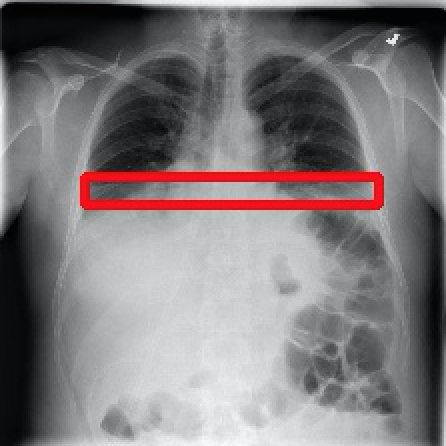

2017年CVPR的一篇“ChestX-ray8”论文[1]首次对医院留存的胸部CT数据库进行人工处理,并通过医学专家分别对8种疾病作标记,形成该领域首个标准的数据库,为胸部医疗的计算机辅助诊断打开了大门,也为后续的研究提供铺垫。CT数据库整理的效果如下图所示,其中红线框内为人工标注的疾病区域:

Atelectasis Cardiomegaly Effusion Infiltrate

Mass Nodule Pneumonia Pneumothorax

图2.1 胸部数据集示例

目前为止,数据集已经达到了14个疾病的分类结果,每张图的大小为1024×1024,少数图片附有由专家标注的病理区域,数据集共有112120张图片,来源于30805个不同的病人,其中51708张图片被标注有疾病,其余则为无病。可以看出无病的数据较多,对有病的特征学习可能较低,相关的学习加速收敛的方法将在2.4节讲解。